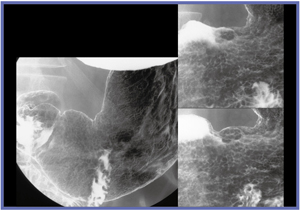

FPD装置1号機は,透視が見えにくい状態で撮影されたが,非常に精細な画像を得ることができた(図1,2)。偶然にも被検者が胃がんUc(表面陥凹)であったことも,評価を行う上で良い条件となった。1号機の評価は,非常にきれいに写るの一言に尽きる。透視が難しいことが大きな課題となっていたが,98年に現在の透視技術の完成に至った。

![]() 図1 FPD装置1号機の撮影像 わずかな表面陥凹が確認できる。 |

![]() 図2 FPD装置1号機の撮影像 アレアが喪失した部分が広がった表層拡大型胃がん |